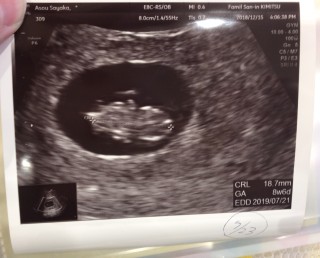

8週4日目 エコー

8週4日目 エコー- 今日は妊婦検診でした。今日で8週と4日目です。 ところが前回まではっきりと確認できていた心拍が今回は確認できず。 胎児はしっかりと週数通りに大きくなっているのですが・・・。 自分でもエコーを見た瞬間に分かりました。排卵後 16日目 妊娠4週2日 超音波検査で胎胞(GS)が見えてきます(15mm) 排卵後 17日目 妊娠4週3日 以後妊娠5週0日まではGSは毎日1mmずつ大きくなります 妊娠5週目以降は、GSの成長が人によって異なります 排卵後 23日目

38 週 4 日 エコー 妊娠8週4日(8w4d)の超音波(エコー)写 妊娠8週4日(8w4d)の超音波(エコー)写真 妊娠8w4d 名前Monri 年齢38 妊娠週8w4d 初期で何かと心配な時期ということで前回から1週間後に再診。順調に177cmへ成長していました!心拍も問題なし。 9週4日(9w4d・男の子)|もぞ1224 さん(29歳) エコー写真撮影時のエピソード: はじめに受審したときのエコー写真は、小さな豆粒のようなものがうつっていた。それからそんなに時がたたないうちに、人の形になって小さな生命を実感した。ママにエールさんの妊娠7週目のエコー写真 2度"逆子"になった胎児はもう小学生! 子どもと共に読み返した当時の日記&エコー画像 画像中央のとの間が赤ちゃんで、上の丸い頭のようなものが赤ちゃんに栄養を送る袋(卵黄嚢)だと教えてもらいまし

妊娠8週4日 8w4d の超音波 エコー 写真